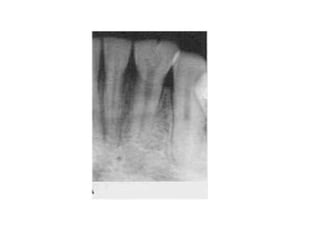

9. Taurodontism

Body dari gigi yang taurodont tampak

memanjang dan akarnya pendek.